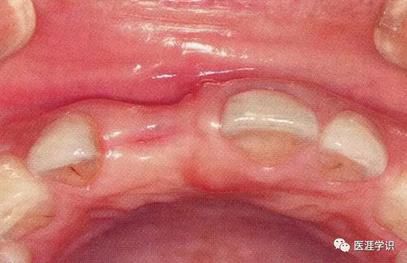

[拔牙造成的牙槽嵴凹陷]

▲圖1-1

右上1拔牙前狀態(tài)。

▲圖1-2

右上1拔牙后2個(gè)月的狀態(tài)。唇側(cè)骨板較薄時(shí),

在拔牙后的牙槽骨吸收會(huì)很明顯。

▲圖1-3

在拔牙時(shí)如果不小心破壞了唇側(cè)牙槽骨的話(huà),血塊就無(wú)法從唇側(cè)滲透,在拔牙窩形成凹陷部,造成的結(jié)果就是修復(fù)體的橋體部分發(fā)生美觀問(wèn)題。